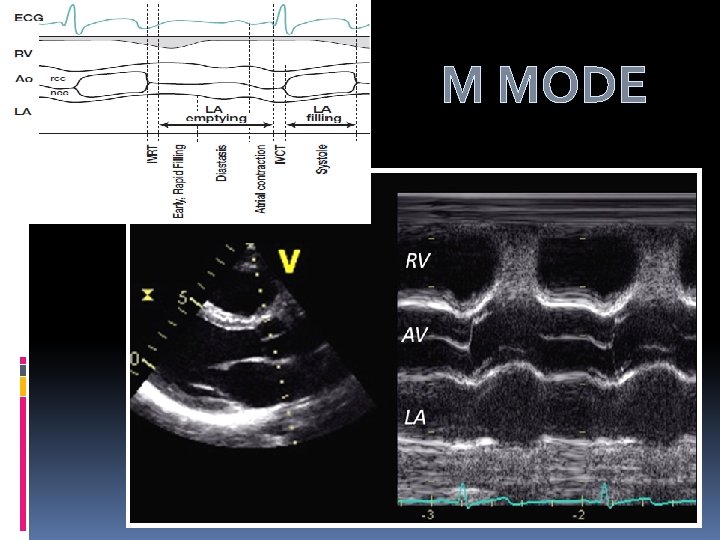

M MODE

M Mode- Aortic Stenosis v Maximal aortic cusp separation (MACS) Vertical distance between right CC and non CC during systole Aortic valve area MACS Measurement Predictive value Normal AVA >2 Cm 2 Normal MACS >15 mm 100% AVA>1. 0 > 12 mm 96% AVA< 0. 75 < 8 mm 97% Gray area 8 -12 mm …. . De. Maria A N et al. Circulation. Suppl II. 58: 232, 1978